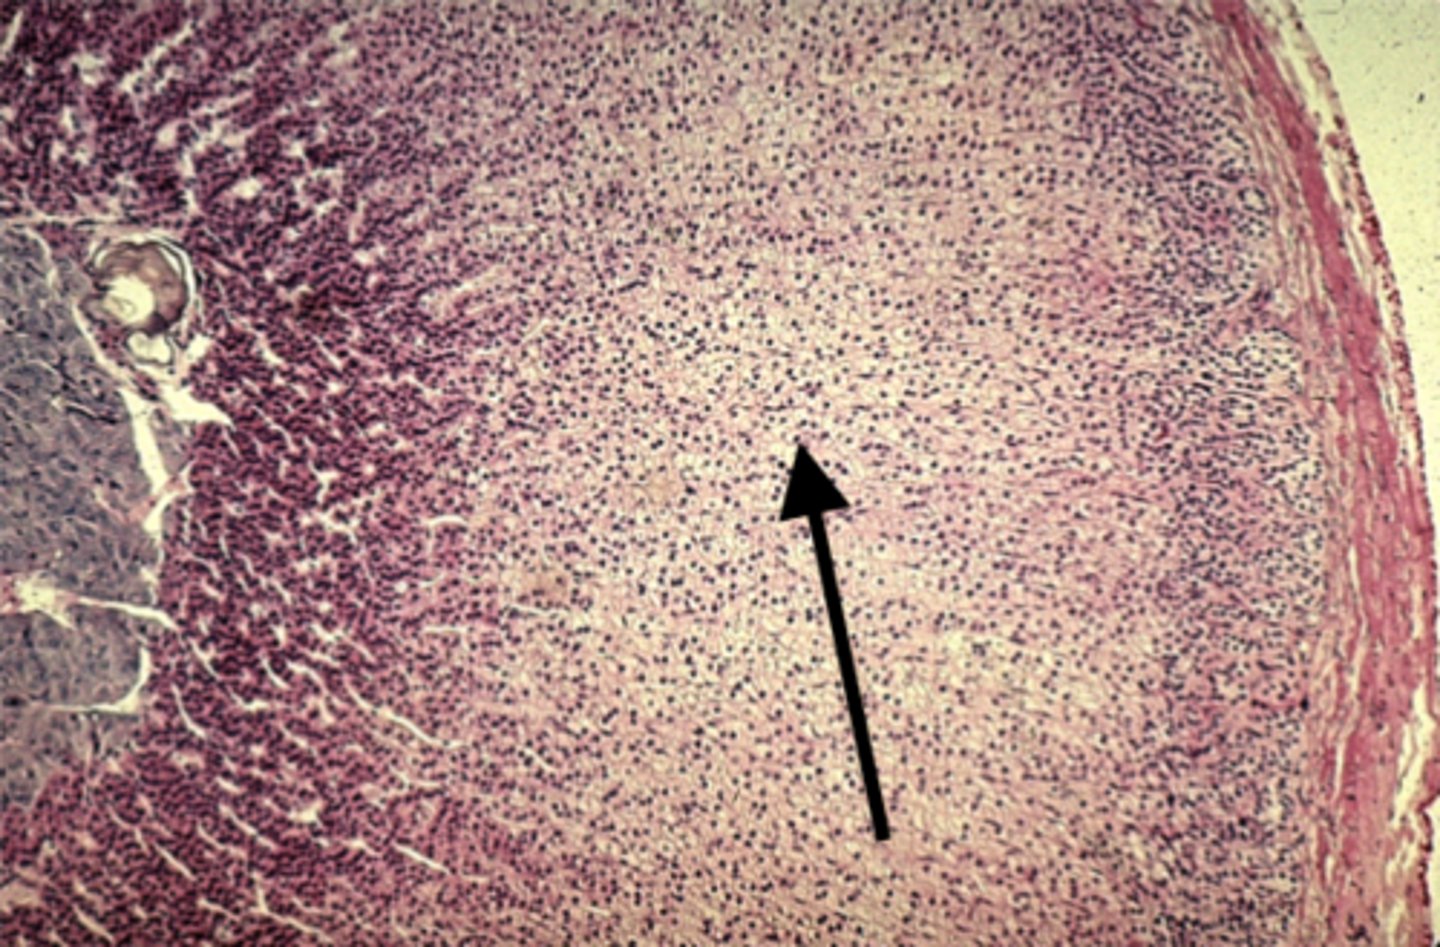

Adrenal gland

what is this?

Zona fasciculata

what is this pointing to?

Zona reticularis

what is this pointing to?

medulla

what is this pointing to?

Cortisol

Zona fasciculata secretes

Aldosterone

Zona glomerulosa secretes

Androgens

Zona reticularis secretes

Epinephrine

What hormone does the adrenal medulla secrete?